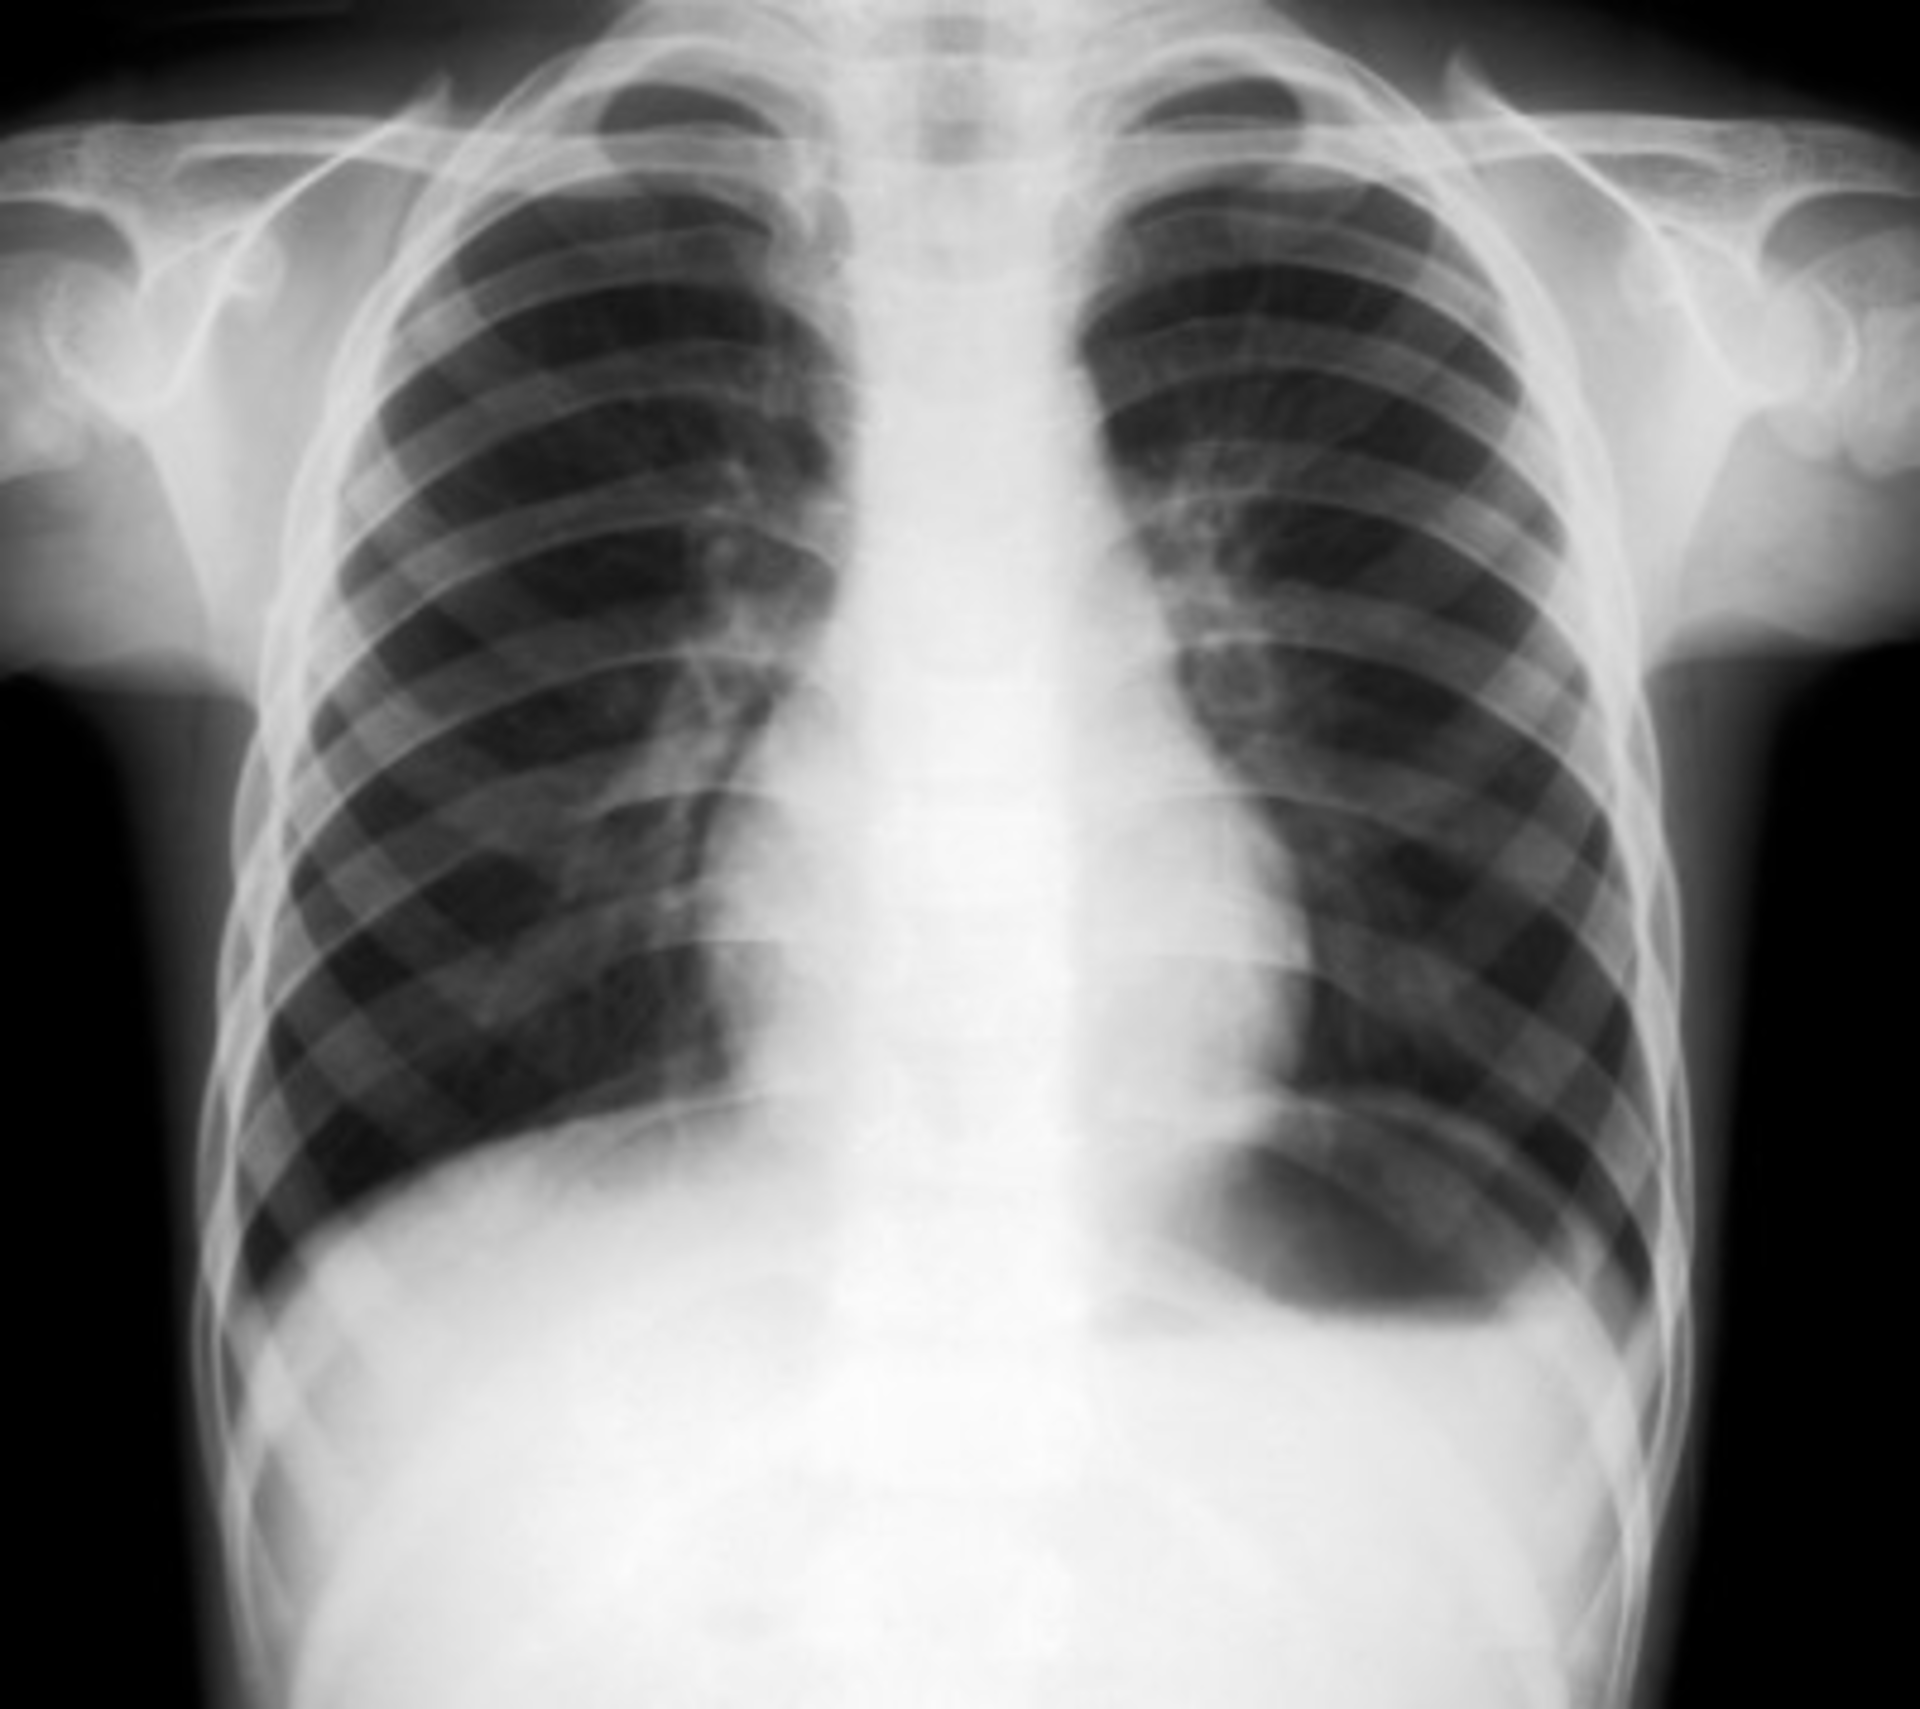

HealthInfoNet and some of Maine’s largest healthcare organizations will begin piloting the nation’s first statewide medical image archive to reduce the cost of storage and transport of electronic medical images and share these images through the health information exchange (HIE).HealthInfoNet, Maine’s statewide HIE, has connected 25 of Maine’s 39 hospitals and will soon add an additional nine hospitals that are ready to connect. The exchange has also linked up 182 physician practices, as well as two long-term facilities and three home health agencies for a total of 1 million individual lives covered by the HIE.For several years, HealthInfoNet has shared radiological reports, says Todd Rogow, director of information technology at HealthInfoNet, but it was clearly a clinician-led effort to get images into the central archive. “Clinicians want to see the image themselves, even though they get the transcribed report [through the HIE]. They want to make their own judgment of the condition. I’ve heard over and over that a picture is worth a thousand words. They want to have those images available.”

Jerry EdsonClinicians will soon have the ability to look at prior studies across organizational boundaries and have immediate access to images in three different ways: through their picture archiving and communication system (PACS), their electronic health record (EHR), or the HealthInfoNet portal.In addition to leveraging the HIE, the archive prepares Maine’s providers for sharing images through the NwHIN Direct and Connect systems. It also supports the development of accountable care organizations and other shared risk-model care delivery structures. Reducing Storage, Transport CostsAn estimated 1.8 million medical images (X-rays, mammograms, CT scans, MRIs, etc.) are generated in Maine each year, totaling more than 45 terabytes of data. The organizations participating in the pilot, which were selected based on their size and volume of images, include Eastern Maine Medical Center (Bangor), MaineGeneral Medical Center (Augusta and Waterville), Maine Health (Portland), and Cary Medical Center (Caribou). Together, these organizations generate 1.4 million of those images. Currently those images are stored in a number of different electronic archives and mostly shared between non-affiliated providers by copying the images to CDs.A formal study of Maine’s four largest health systems showed the cost of storing a study ranged from 50 cents per study to more than $4 a study, while transport costs ranged from $4 to $15. Edson says the industry norm is approximately $12 a study. By consolidating medical images into a single archive, HealthInfoNet estimates that Maine’s providers could save $6 million over seven years through reduced storage and transport costs.“[The archive] is self-sustaining because essentially we are going to be able to offer it on a fee for study basis that is less than the cost of what it’s currently costing them,” says Edson. Interface and implementation costs will be spread over the organization’s five-year contract.Beyond reducing repeat tests and allowing easier image search through a single patient identifier, Edson says another added benefit of the archive will be augmentation of an organization’s business continuity and disaster recovery practices. The five years of onsite storage, as well as complete cloud archival, is being offered less expensively than these organizations current archives, says Edson.HealthInfoNet selected the Round Rock, Texas-based Dell to build and operate the new cloud-based archive through a rigorous RFP process that involved vetting by both Maine clinicians and health information technology professionals. Part of Dell’s offering is an interoperability library that enables compatibility for 30 of the major PACS suppliers and more than 10,000 interfaces for the PACS suppliers different release levels.All pilot sites will be interfaced in parallel and will work together with HealthInfoNet over the next five months to confirm the system design and integrate the service with existing PACS systems and the HIE. HealthInfoNet expects to end the pilot phase in the fall and expand the service statewide by 2013.